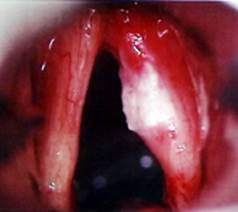

6.2 NEPOSREDNI PREGLED

Za natančnejšo diagnozo je potreben neposredni pregled grla, ki se naredi s pomočjo posebej prirejenega instrumenta - direkto­skopa. Ta poseg, še posebej uvajanje instrumenta, je včasih zelo neprijeten, zato se pregled ponavadi dela v splošni omami. Med posegom lahko zdravnik, kadar je potrebno, odvzame tudi košček bolnega tkiva za histološko preiskavo.Pri neposrednem pregledu vidimo grlo in bolezenske spremem­be brez kakršnegakoli posredo­vanja, kot že samo ime pove, nepo­sredno.

Slika 11a

Pregled delamo v splošni omami in ni časovno omejen, zato je pregled izredno natančen (sl. 11a).